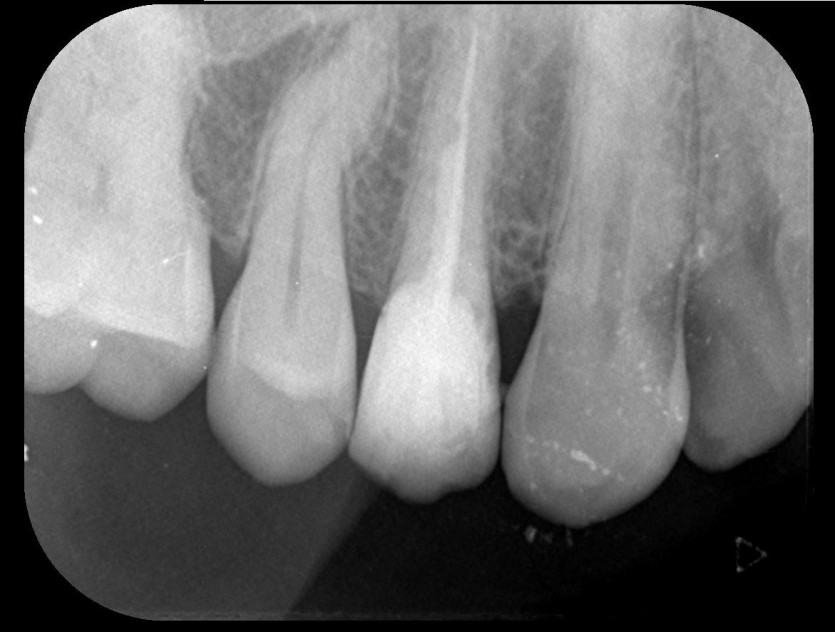

임플란트 사례